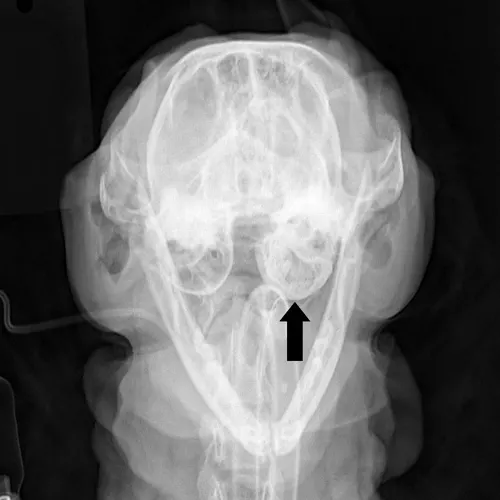

Chest radiography can rule out lower respiratory and metastatic disease (if malignancy is suspected). Skull radiographs —including open-mouth, lateral, lateral oblique (left and right), and ventrodorsal views—are also obtained (Figures 2 and 3). False-negative results are common with bulla radiographs. Computer tomography (CT) is sensitive for the detection of middle ear involvement.

FIGURE 3 The very large soft tissue density (arrows) in the pharyngeal region of this lateral skull radiograph represents a large inflammatory polyp.